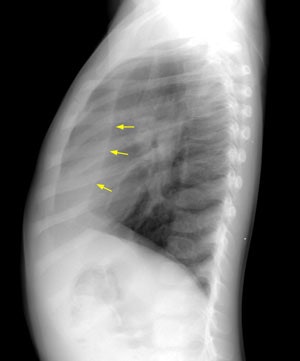

Scimitar Syndrome:

In Scimitar syndrome the heart and mediastinum are shifted towards the involved side (dextropositioning of the heart in this case) due to the pulmonary hypoplasia. There is compensatory overexpansion of the opposite lung. The thoracic cage is smaller on the affected side with approximation of the ribs, although this may not be evident at birth. The anomalous draining vein produces a curvilinear vascular shadow which courses towards the hemidiaphragm and has the appearance of a Turkish sword (or scimitar- blue arrows). A retrosternal opacity may be seen on the lateral exam (yellow arrows). This density has previously been erroneously ascribed to extrapleural areolar tissue anterior to the visceral pleura of the right lung. In actuality, this density is produced by the interface of the displaced mediastinum with the aerated, small right lung.Click on small images to enlarge